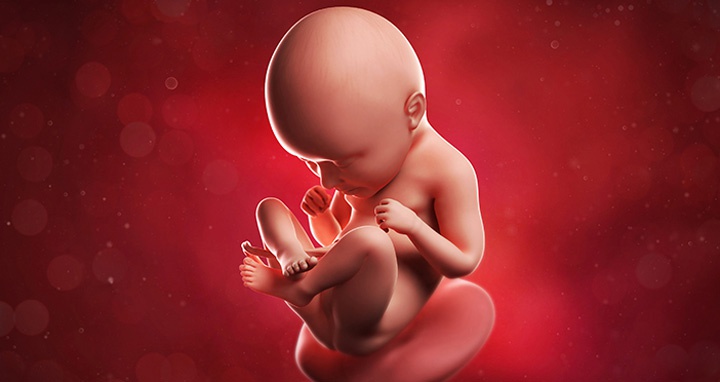

Как выглядит ребенок на 35 неделе беременности

На середине третьего триместра значительных изменений не происходит. Ребенок наращивает мышечную и жировую ткань.

Плод полностью сформирован. В подкожной жировой клетчатке продолжается отложение жира, кожа разглаживается и бледнеет, становится почти розовой, лишенной пушковых волос. Лануго сохраняется только в естественных складках тела. Ногти почти закрывают ногтевые ложа, а щечки округляются, лицо приобретает мягкие черты. Глаза остаются закрытыми, радужная оболочка принимает генетически заложенный цвет, но у всех младенцев пока голубые.

Большие половые губы у девочек скрывают малые, а у мальчиков яички окончательно опустились в мошонку.